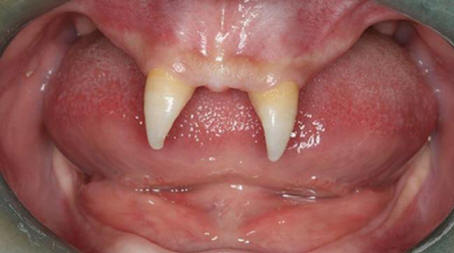

Il ragazzo cinese crebbe due denti anteriori molto affilati, dentro facendolo sembrare un vampiro. Nel dicembre 2012 la madre di nome Wang Hui portò suo figlio Wang Penfei nel locale ospedale per esame. Chongqing Municipal Boy After la nascita sta crescendo molto male e nella sua bocca sono comparsi due acuti zanna.

Wang Hui ha cercato di scoprire il motivo dell’apparizione del figlio di questi formazioni anormali e visitato innumerevoli medici, ma non ha portato molto successo. Medici di Southwestern Hospital dice che suo figlio può essere fatto chirurgia solo quando diventa adulto.

foto da fonti aperte

Il costo di questa operazione può variare da 70.000 a 80.000 RMB, sono circa $ 15.000. Secondo Wang Hui, suo figlio sta diventando sempre più ritirato, e spesso combatte con i compagni di classe, che bisbigliano di lui o lo guardano con aria interrogativa.